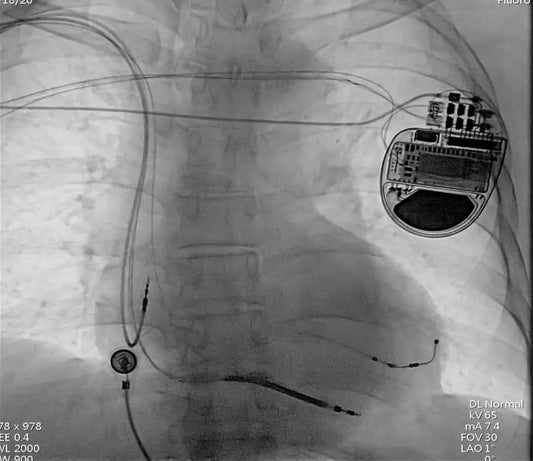

A multidisciplinary team at Fuwai Hospital successfully performed a complex 15-hour procedure to implant a Cardiac Resynchronization Therapy Defibrillator (CRT-D) in a patient with advanced heart failure, expanding the possibilities...